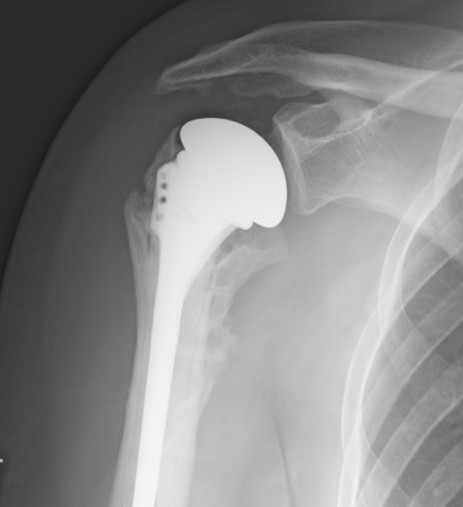

Options

Overstuffed aTSARevision to revTSA

Revision to reverse TSA

Shield et al. JAAOS 2019

- revision for cuff failure to rTSA compared to primary rTSA

- increased complications and worse patient outcomes in the revision group